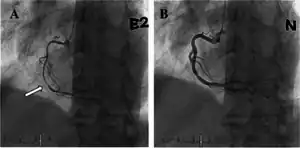

| a) Occlusion of mid portion of right coronary artery b) after injection of intracoronary nitrate shows resolution | |